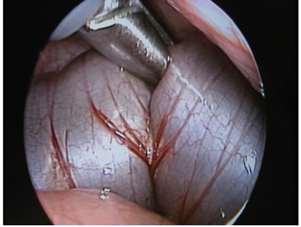

The grasper is used to hold the part of the colon chosen for the stoma, which is pulled up to the trocar (Figure 2); the trocar is then withdrawn. The grasper is used to bring the bowel out through the abdominal-port opening. After displacing the marginal artery, the colon is divided outside the abdominal cavity. The effluent is suctioned away to prevent peritoneal contamination. This step decompresses the intestine, giving the neonate enough relief and relaxation for completion of the procedure. The decompression also creates space for further examination of the bowel and other abdominal structures.

Figure 2 The figure shows an intra-abdominal view of the grasper holding the left colon.